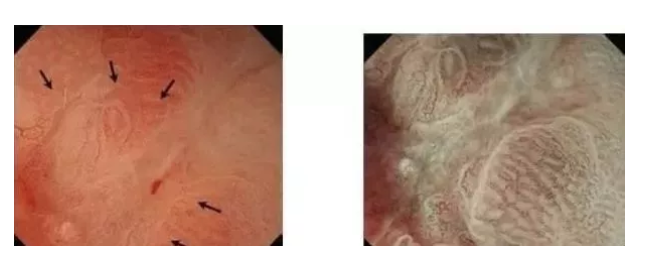

但是,有一种情况例外,就是肿物不是胃黏膜上长的,而是黏膜下长出来的,通常黏膜是光滑的,比较常见的就是胃间质瘤(GIST),见下图。

一旦怀疑是间质瘤,就不应该取活检,容易穿刺破裂,导致转移和复发。

早期胃癌如图所示,有时很难与胃溃疡分辨。